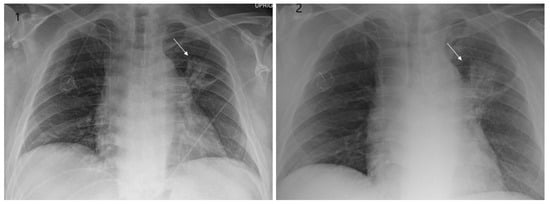

Even though X-ray is non-specific to pneumonitis, it is usually the first investigation performed. During the early phases, the most common finding on chest radiograph is perivascular haziness which frequently progresses to alveolar opacities [39]. Chest radiographs can show ground-glass opacity and/or consolidation in the radiation port. Consolidation usually has a nodular appearance but can be more confluent/lobar along with the irradiated port. Findings can be seen outside the radiation port as well. Some uncommon findings are ipsilateral pleural effusion with or without adjacent atelectasis [66]. Chest radiograph can also show bilateral interstitial infiltrates mimicking heart failure or acute respiratory distress syndrome (ARDS) [69,70]. All irradiated patients usually have some degree of abnormalities in the X-rays. Some fail to show any radiographic evidence of lung injury with pneumonitis. Early features exhibiting mild opacification of vascular markings are common, with later stages showing dense opacities. A radiographic straight-line effect may indicate the direction of the radiation port along the lines of pneumonitis [39,71] (Figure 1).

Figure 1.

Chest X-ray showing radiation pneumonitis Image 1—Frontal chest X-ray showing left upper lobe mass (arrow), the patient also had a right internal jugular port placed. Image 2—Post radiation treatment frontal chest X-ray showing increasing alveolar and interstitial opacities in the left upper lobe and in the left lower lobe in a patient suspected of radiation pneumonitis.